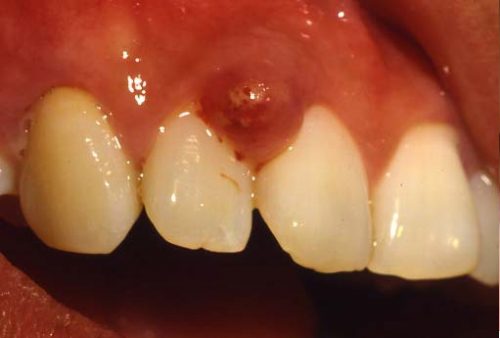

دلایل سیستمیک بزرگ شدن لثه

برخی وضعیتهای سیستمیک و فیزیولوژیک وجود دارند که ممکن است باعث و علت متورم شدن لثه شوند از جمله بارداری، عدم تعادل هورمونی و لوکمی. در زیر یک نمونه از عکس ورم لثه مربوط به بارداری نشان داده شده است.

بزرگ شدن لثه ناشی از یک وضعیت سیستمیک معمولا با حل شدن یا درمان مشکل اصلی با در مورد بارداری با زایمان، برطرف میشود. در این موارد هم مانند تورم لثه ناشی از مصرف دارو، رعایت بهداشت مناسب احتمال بزرگی لثه را کاهش میدهد.